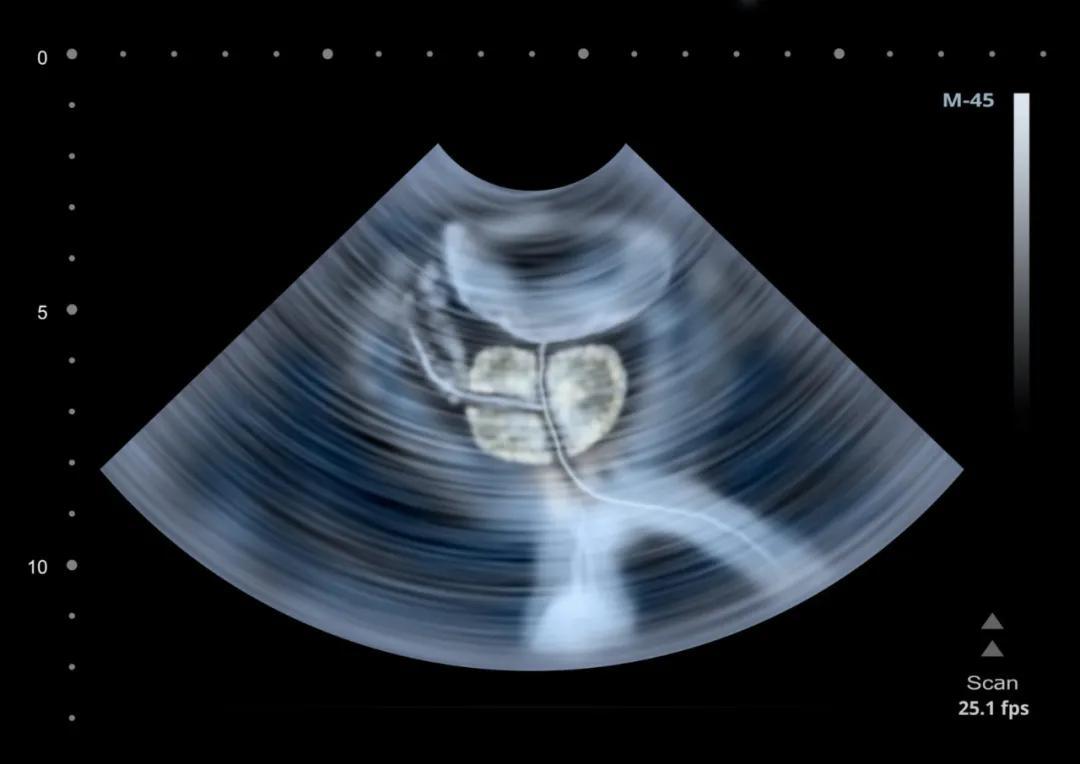

前列腺是影響男性健康的“重災區”,增生、結石及鈣化、囊腫都是常見的前列腺病變。